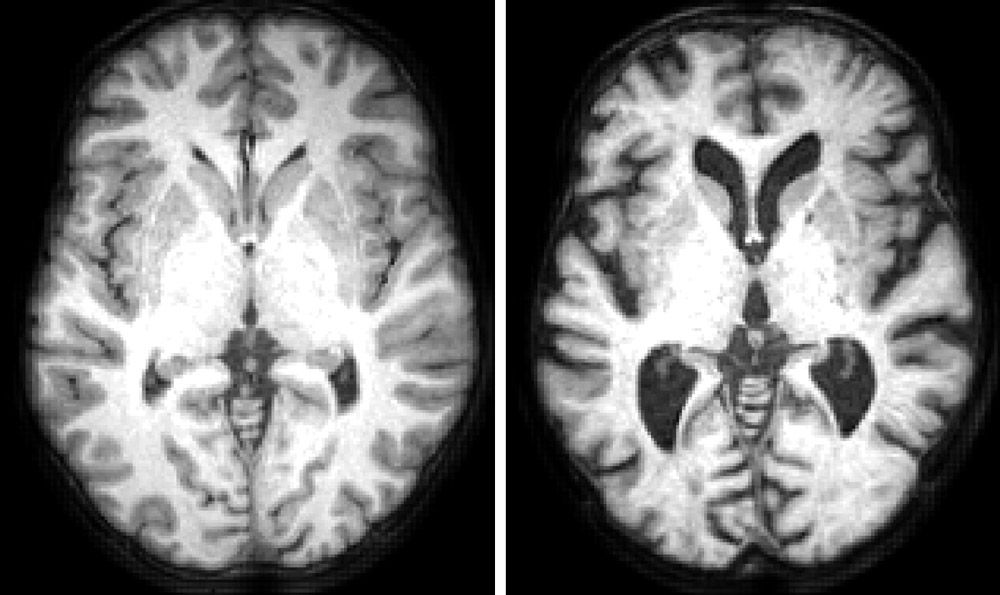

The Cambridge Centre for Ageing and Neuroscience (Cam-CAN) is a large-scale research project launched in 2010 to understand how individuals can best retain cognitive abilities into old age. Cam-CAN is an interdisciplinary effort in which researchers from psychology, neuroscience, psychiatry, engineering, and public health use various brain imaging techniques, such as structural and functional magnetic resonance imaging (MRI) and magnetoencephalography (MEG), to measure age-related changes in brain structure and function. The structure of brains changes dramatically as we age (Figure 1), so how do some people maintain many of their cognitive abilities despite these changes?

Figure 1. Structural MRI images showing a horizontal section through a typical healthy 19-year old and the brain of a typical healthy 86-year old.

Figure 1. Structural MRI images showing a horizontal section through the brain of a typical healthy 19-year old (left) and typical healthy 86-year old (right). The dark holes (ventricles) in the older brain are larger because the gray matter (convolutions around edge of brain) and white matter (remaining lighter material) have shrunk over the years.